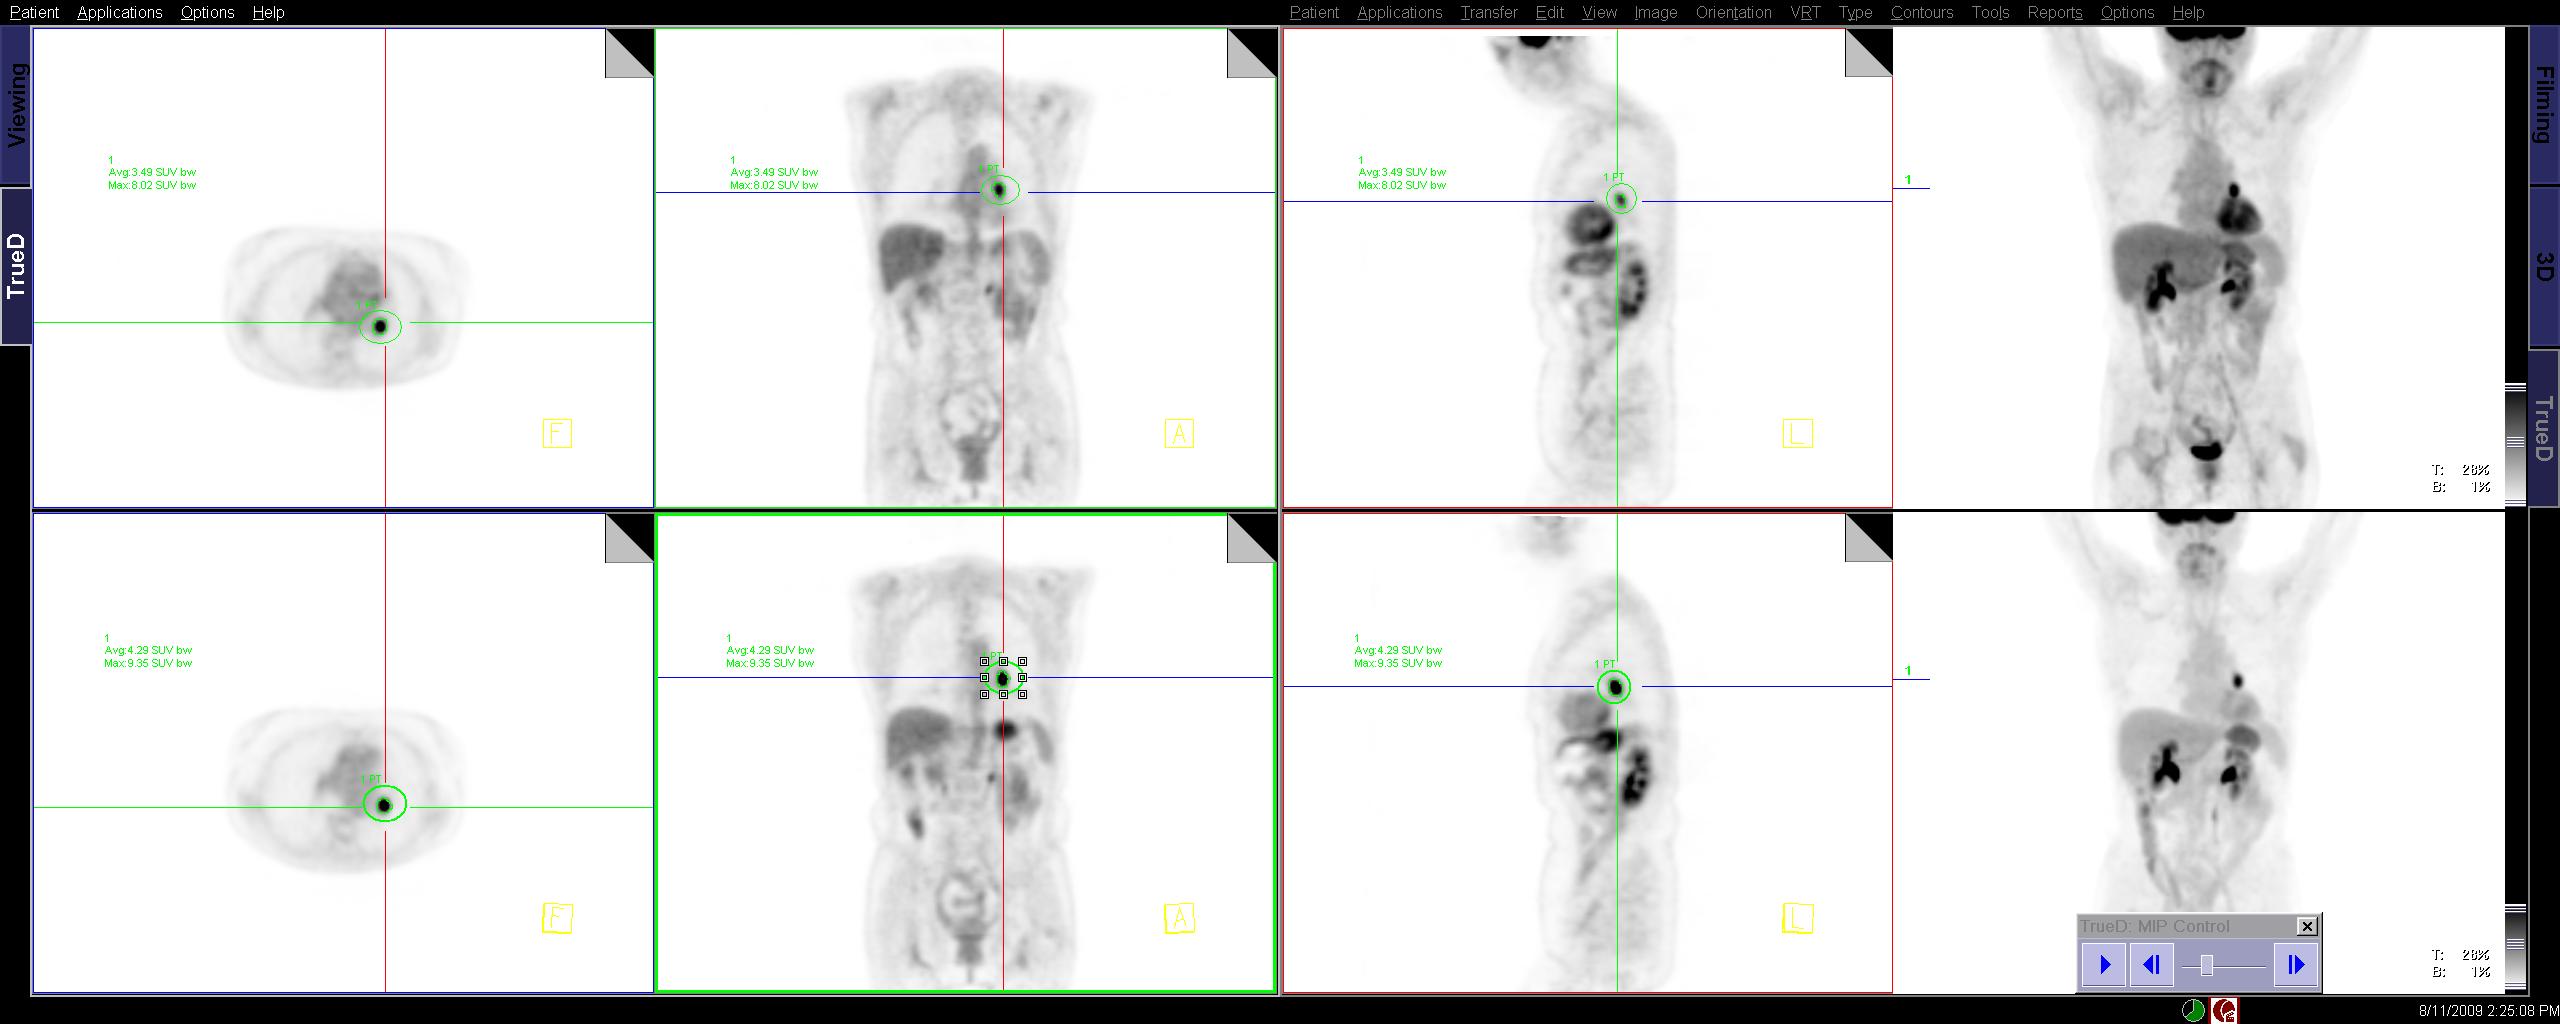

== Display to use as reference for dev == | == Display to use as reference for dev == | ||

[[image:PETSUV.jpg]] | [[image:PETSUV.jpg]] | ||